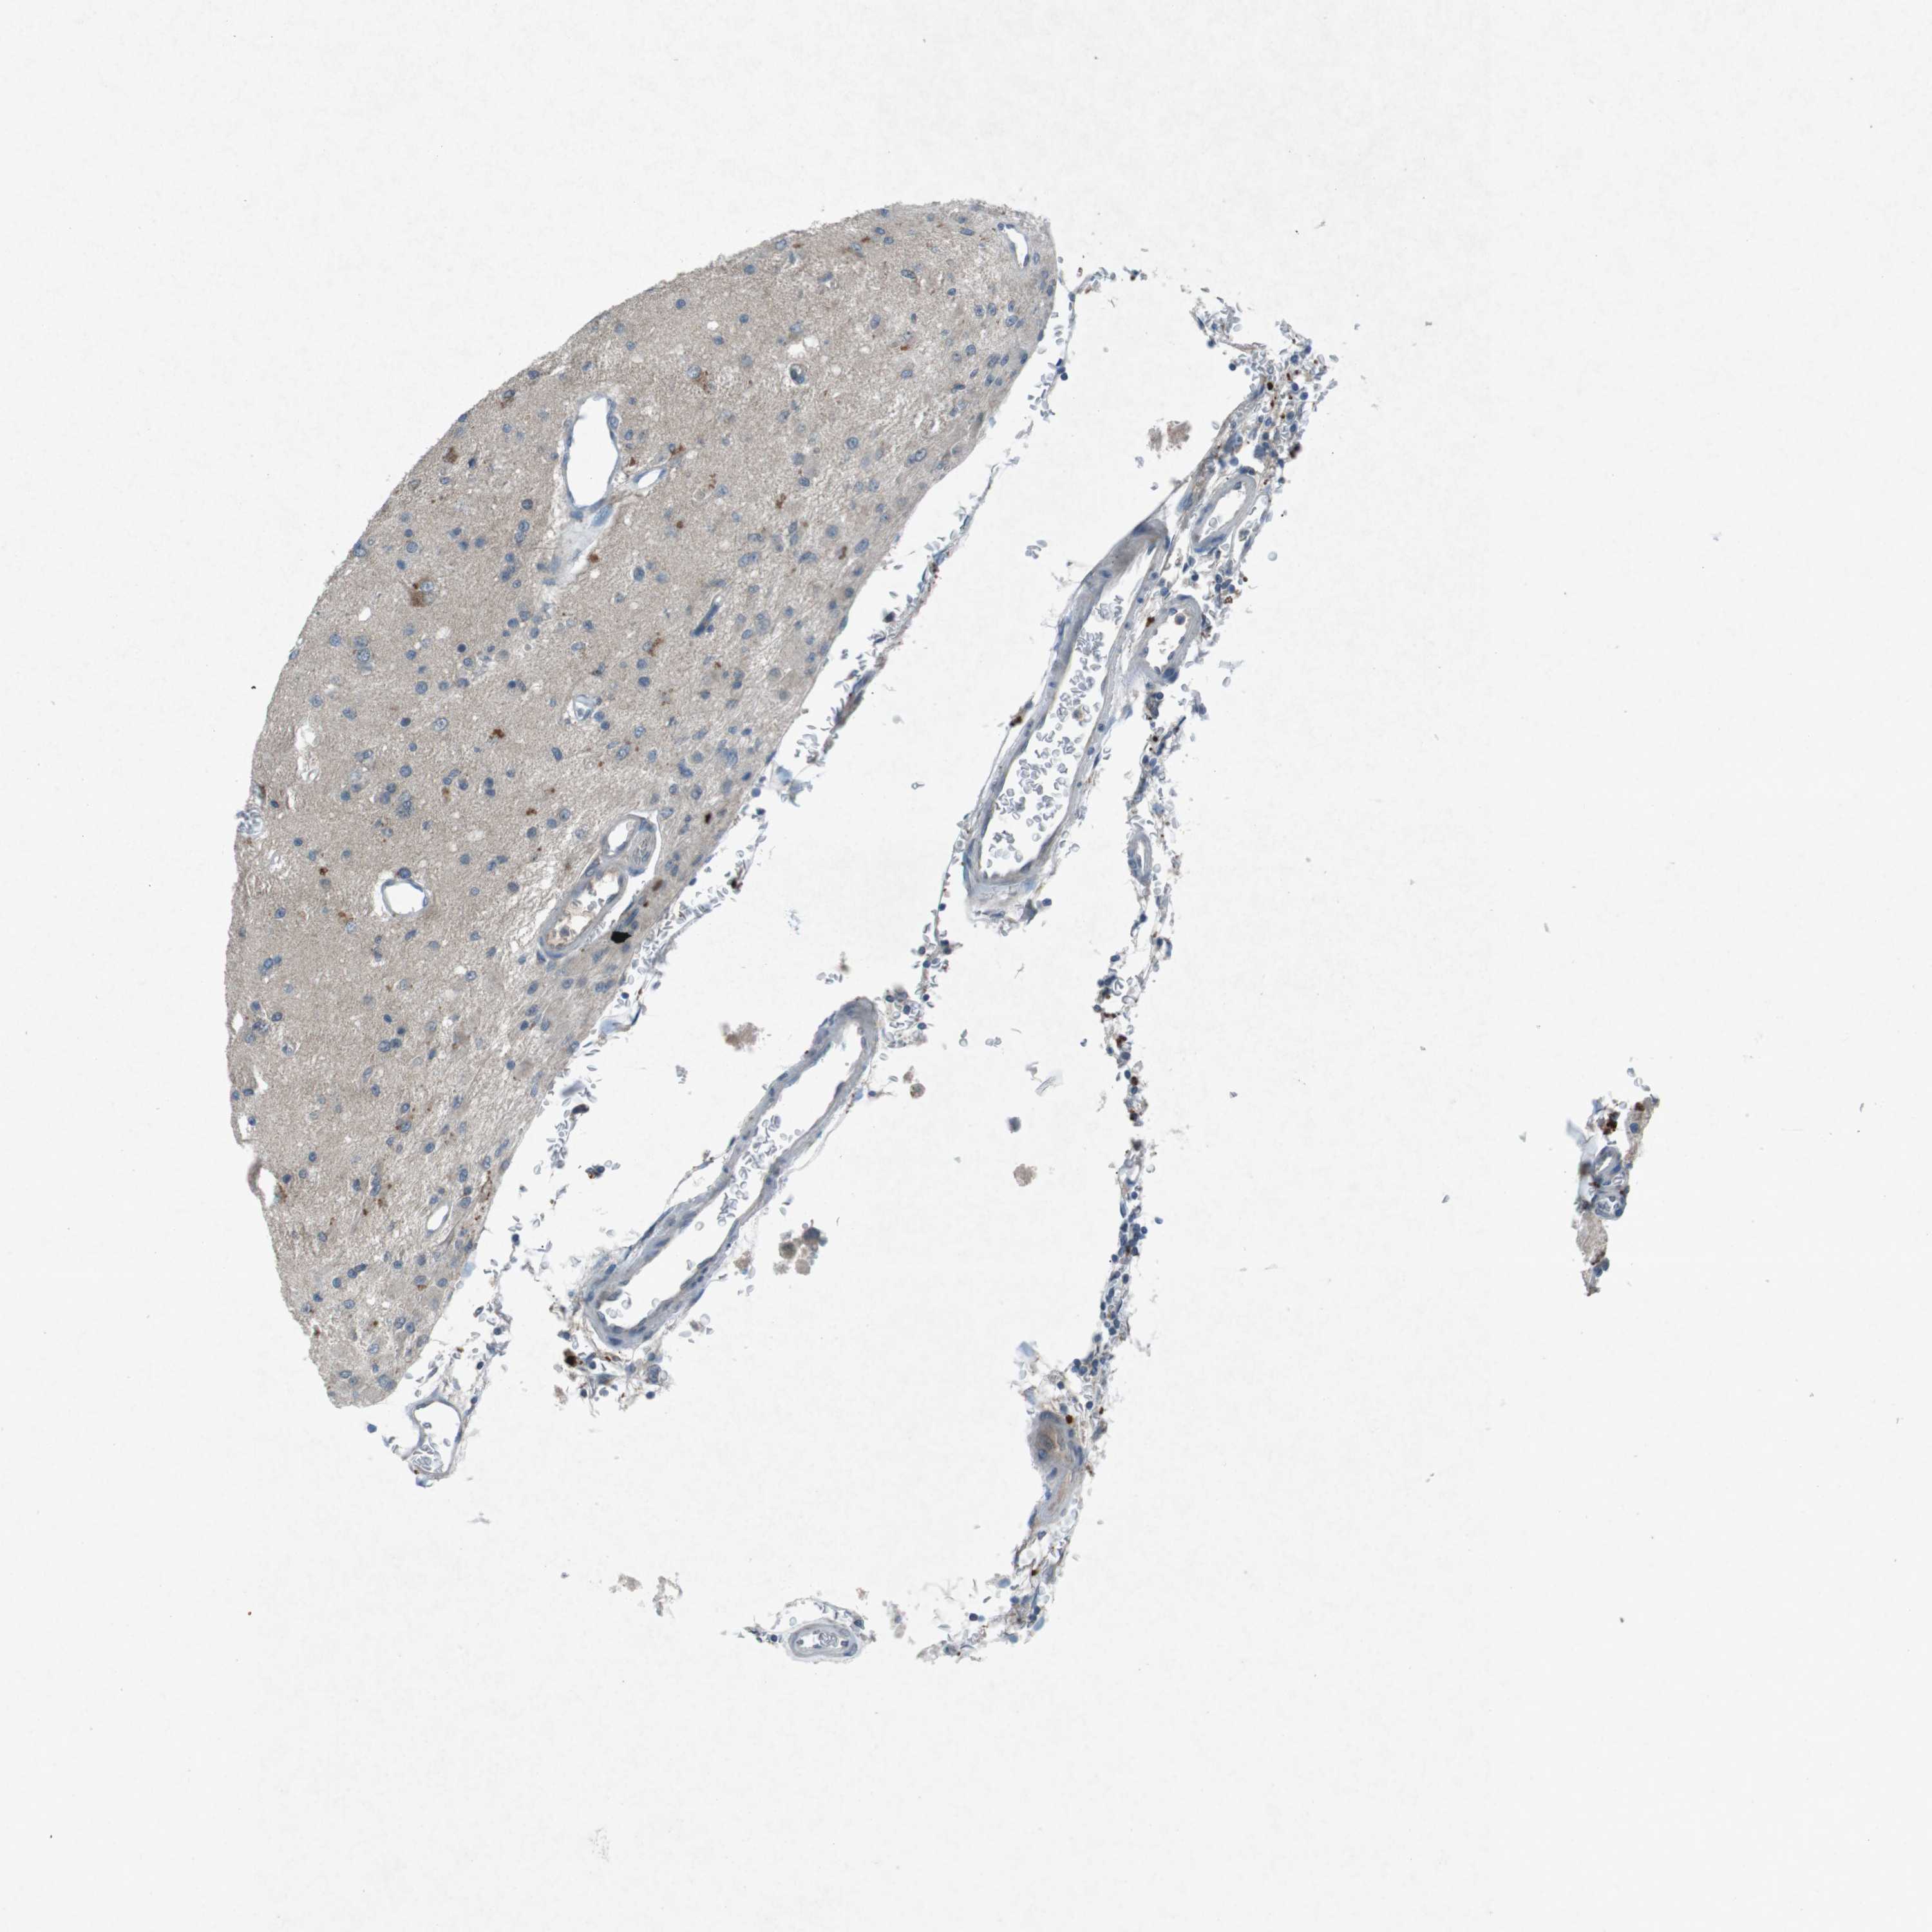

GLIOMA - Protein expressioni

A mouse-over function shows sample information and annotation data. Click on an image to view it in a full screen mode. Samples can be filtered based on level of antibody staining by selecting one or several of the following categories: high, medium, low and not detected. The assay and annotation is described here.

Note that samples used for immunohistochemistry by the Human Protein Atlas do not correspond to samples in the TCGA dataset.

Antibody stainingi

Antibody staining in the annotated cell types in the current human tissue is reported as not detected, low, medium, or high, based on conventional immunohistochemistry profiling in selected tissues. This score is based on the combination of the staining intensity and fraction of stained cells.

Each image is clickable and will lead to virtual microscopy that enables deeper exploration of all samples and also displays staining intensity scores, fraction scores and subcellular localization as well as patient and tissue information for each sample.

Antibody CAB016545

Staining

High

Medium

Low

Not detected

Intensity

Strong

Moderate

Weak

Negative

Quantity

>75%

75%-25%

<25%

None

Location

Nuclear

Cytoplasmic/membranous

Cytoplasmic/membranous,nuclear

Glioma, malignant, High grade

Glioma, malignant, Low grade